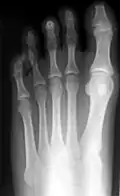

Hammerzehen vor einer operativen Korrektur -

Hammerzehen nach der operativen Korrektur; deutlich sind die verkürzten dritten Glieder der drei inneren Zehen erkennbar (Operation nach Hohmann). Bei dieser OP wurde auch der Hallux valgus korrigiert. -